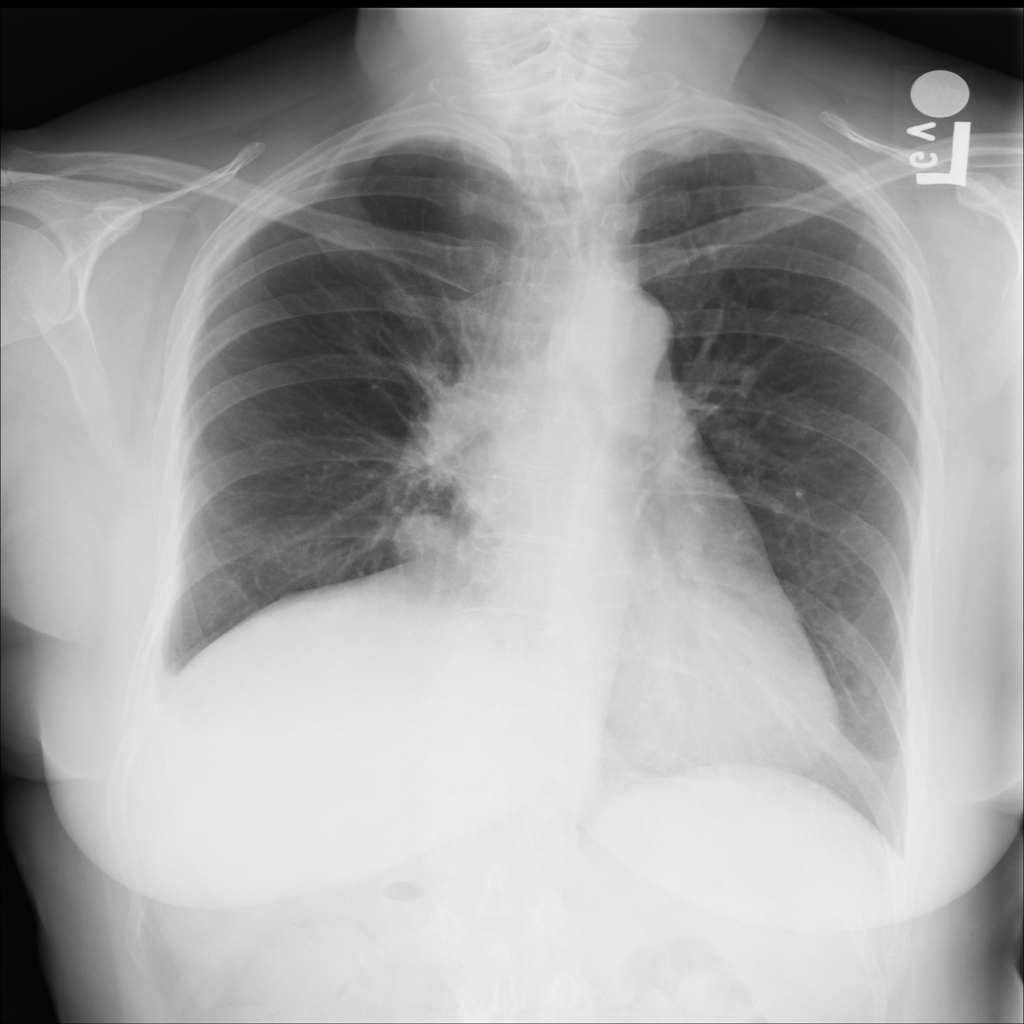

Mass

A mass is a larger focal opacity or lesion seen on the image. It is a descriptive finding that can have several causes and usually needs more imaging or clinical context to characterize.

PAT-50E5 · IMG-008Mass

PAT-50E5 · IMG-008

PA